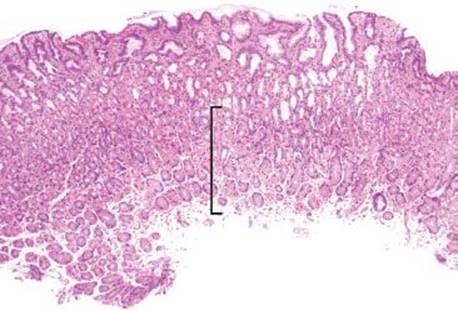

Figure 2.235 Iron pattern C/“gastric glandular siderosis”. This iron pattern can be one of the more difficult to recognize because of the subtle and uniform findings that are not very apparent at low power (bracket). Nonetheless, it can be critical to appreciate since it indicates iron overload and may prompt genetic testing for hereditary hemochromatosis, in the appropriate clinical setting. The more common setting, however, is a transfusion dependent patient, as in this case. This patient had a history of lymphoma, bone marrow transplant, and was known to have iron overload syndrome based on the history of extensive blood transfusions.

Gastric iron deposition is seen in up to 3.8% of upper tract biopsies (Fig. 2.228).23,24,183–185 In a study of 500 gastric biopsies, the deposition was demonstrated in three generalized patterns. Pattern A (also referred to as “nonspecific gastric siderosis”) was the most common subpattern and involved 2.2% of specimens (Figs. 2.229 and 2.230). This subpattern was associated with prior mucosal microhemorrhages, and the subtle depositions were predominantly identified within macrophages and stromal cells of the lamina propria. Pattern B (also referred to as “iron pill gastritis”) was seen in 0.8% of the biopsies and was consistently associated with ferrous sulfate therapy. This deposition was coarse and crystalline and predominantly identified in the extracellular and most superficial aspect of the biopsy (Figs. 2.231–2.234). In this subpattern, the background mucosa had a reactive gastritis/gastropathy pattern with erosions, ulcerations, and fibrino-inflammatory exudate common. In a separate study of 1,300 gastric biopsies, a similar “iron pill gastritis” injury pattern was detailed.184 This latter group reproduced the identical iron deposits in the laboratory by oxidizing ferrous sulfate tablets, providing clear evidence for the iron origin of these deposits. The mechanism of injury is a bit unclear in this subpattern. Some speculate that the iron pill has a direct caustic effect on the adjacent mucosa, whereas others suggest that the iron deposits may simply colonize previously injured mucosa. Pattern C (also referred to as “gastric glandular siderosis”) was the least common pattern, involving 0.6% of the specimens. This subpattern was associated with iron overload settings, such as hereditary hemochromatosis and multiple blood transfusions. The characteristic deposits were subtle, uniform, and identified in the deep antral and oxyntic glands (Figs. 2.235–2.239). The iron deposits can be highlighted blue with a Prussian blue iron special stain. Recognition is important to help prevent further injury and potential stricture formation (pattern B), to suggest pertinent iron overload evaluation (pattern C), and to avoid overdiagnosing the marked reactive epithelial change as dysplasia.

• Pattern C/“gastric glandular siderosis” is associated with iron overload; the deposits are subtle, uniform, and identified in the deep antral and oxyntic glands.